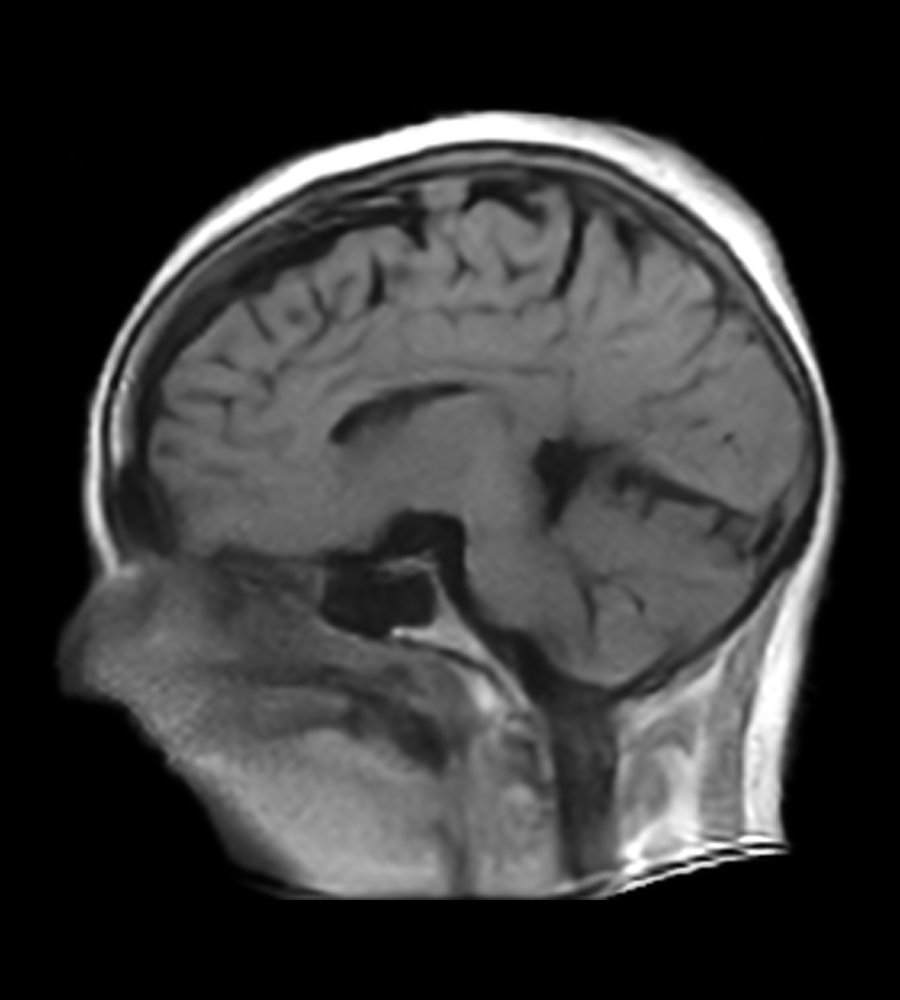

Clinical Images

Clinical Case Types: Headache, Migraine, Multiple Sclerosis, Microvascular Disease, and Tumor Routine Follow-up.

Multiple Sclerosis